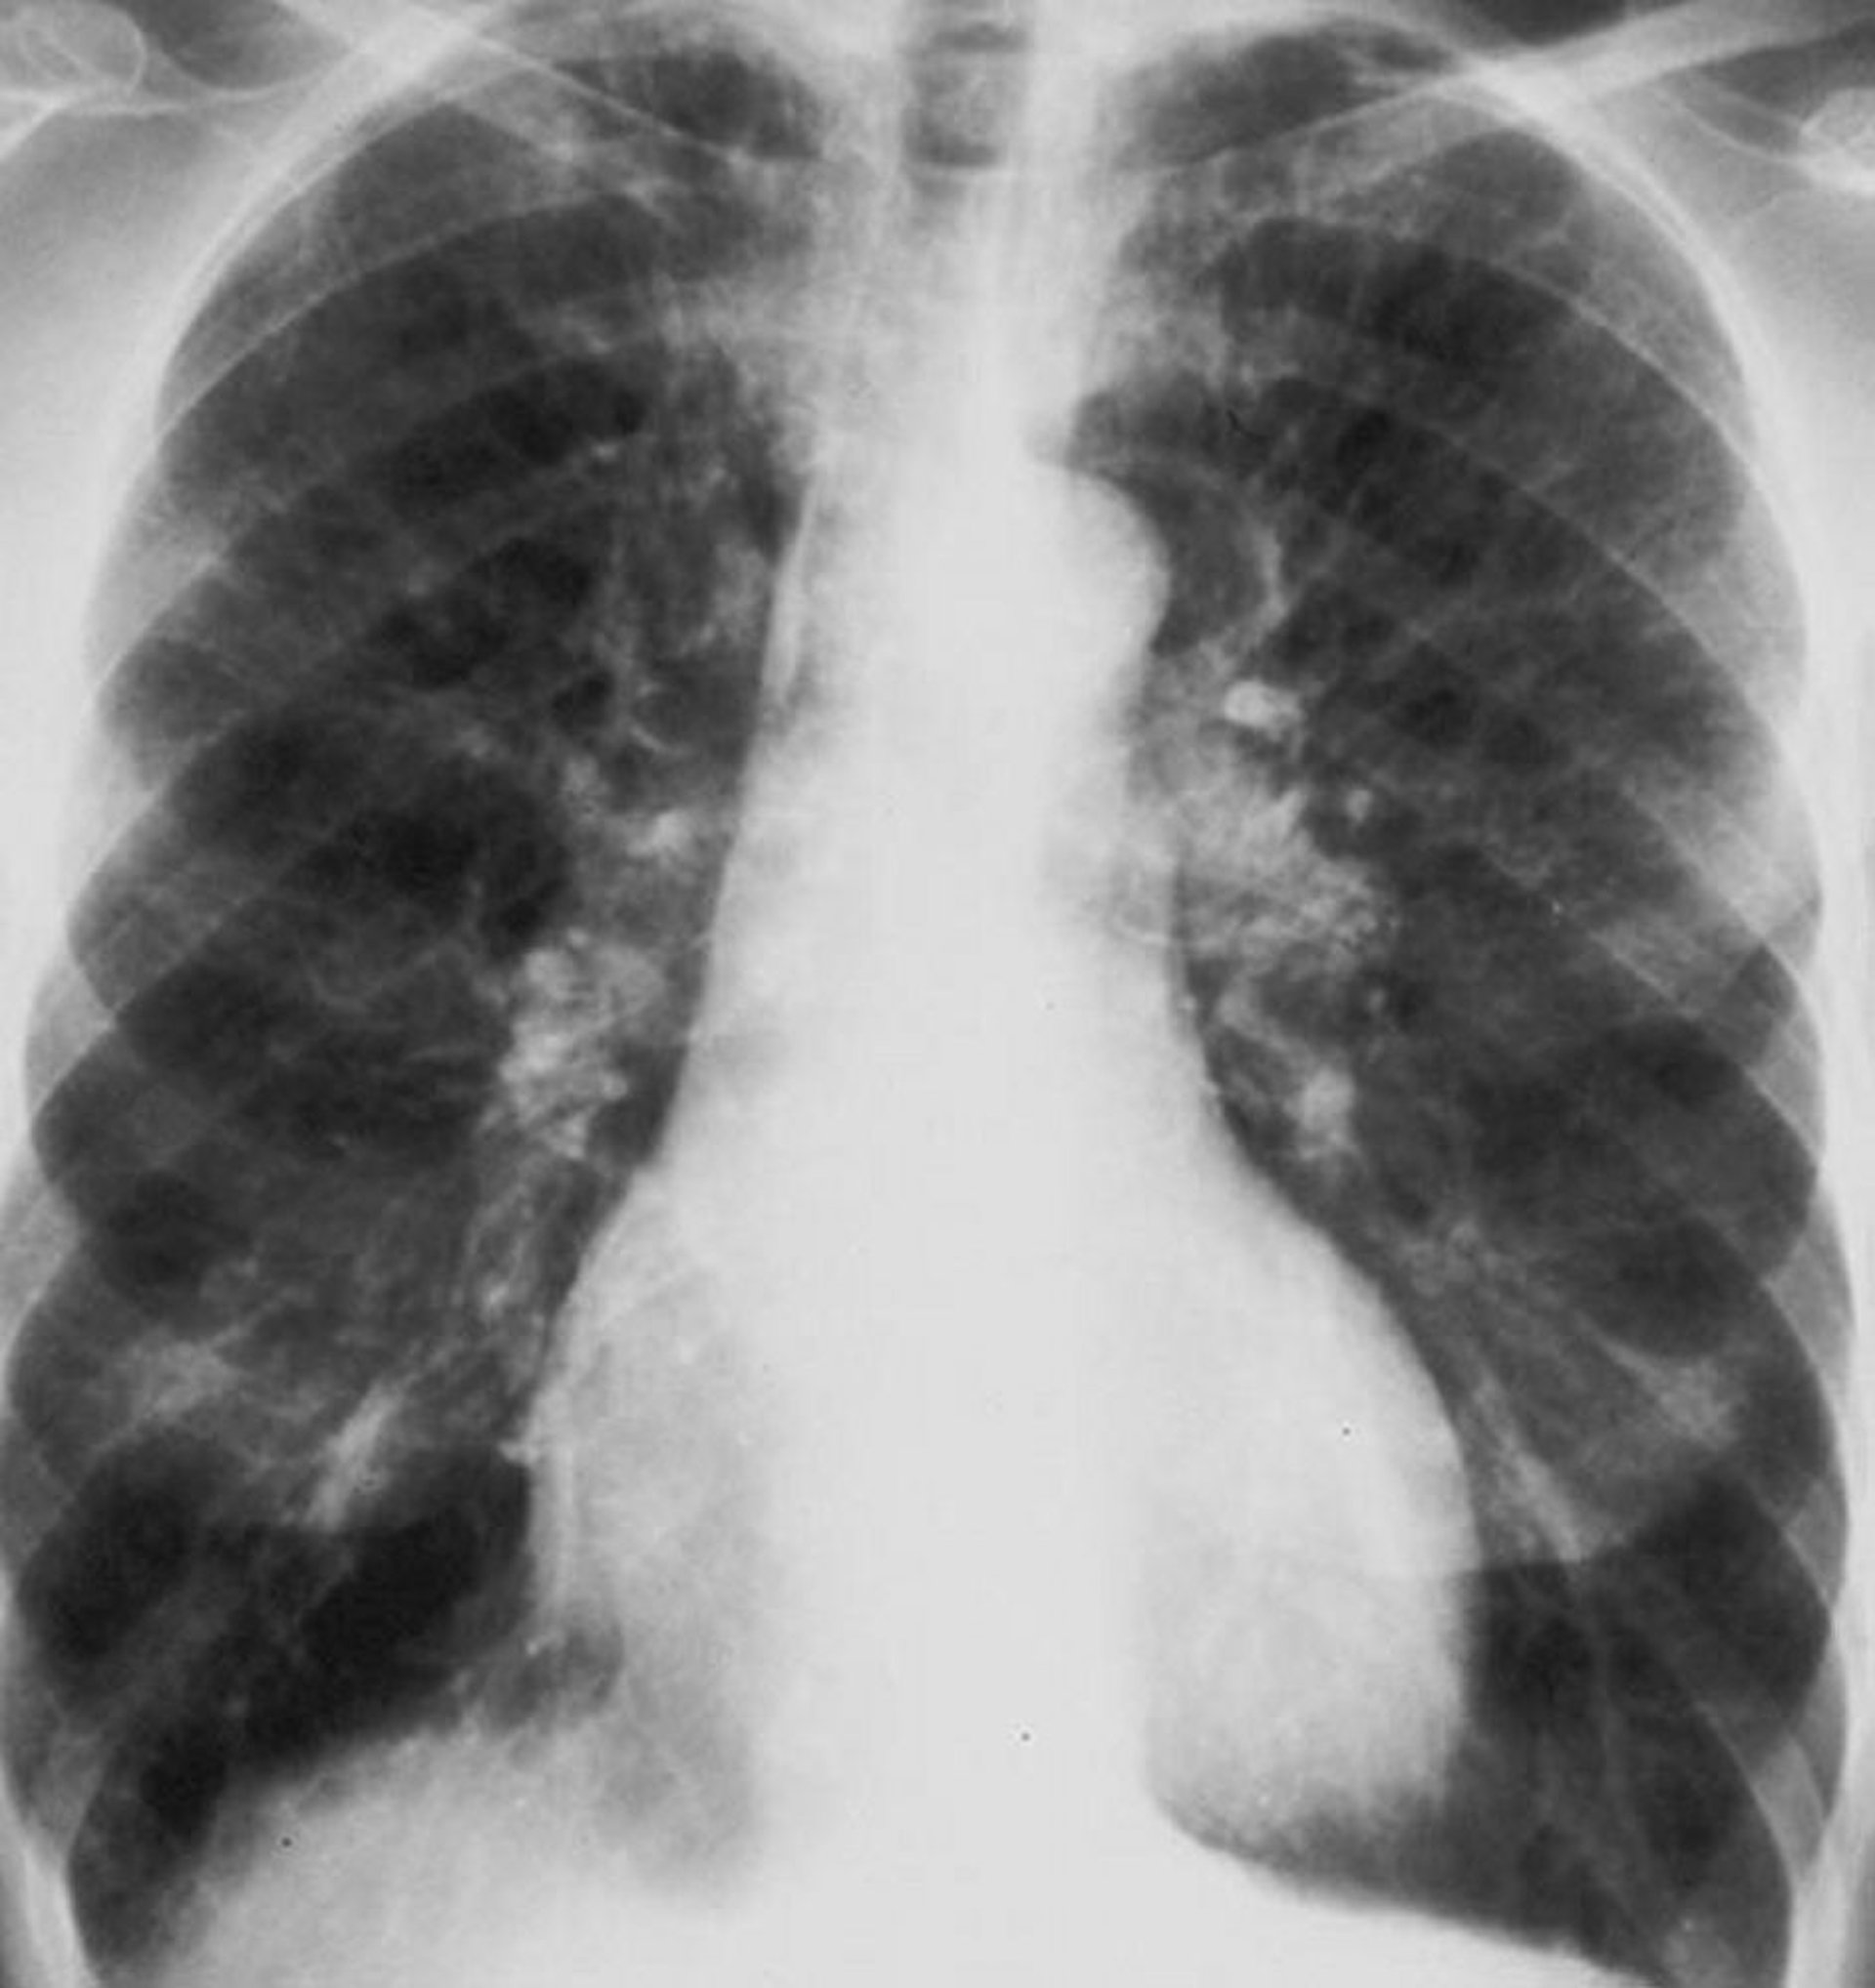

Chronische obstruktive Lungenerkrankung (Röntgenthorax)

Röntgenaufnahme des Thorax bei einem Patienten mit chronisch obstruktiver Lungenerkrankung (COPD). Die Lunge ist überbläht, das Zwerchfell ist abgeflacht, die Gefäßmarkierungen sind vergrößert, und das Herz ist geringfügig vergrößert.

By permission of the publisher. From Barnes P. In Bone's Atlas of Pulmonary and Critical Care Medicine. Edited by J Crapo. Philadelphia, Current Medicine, 2005.